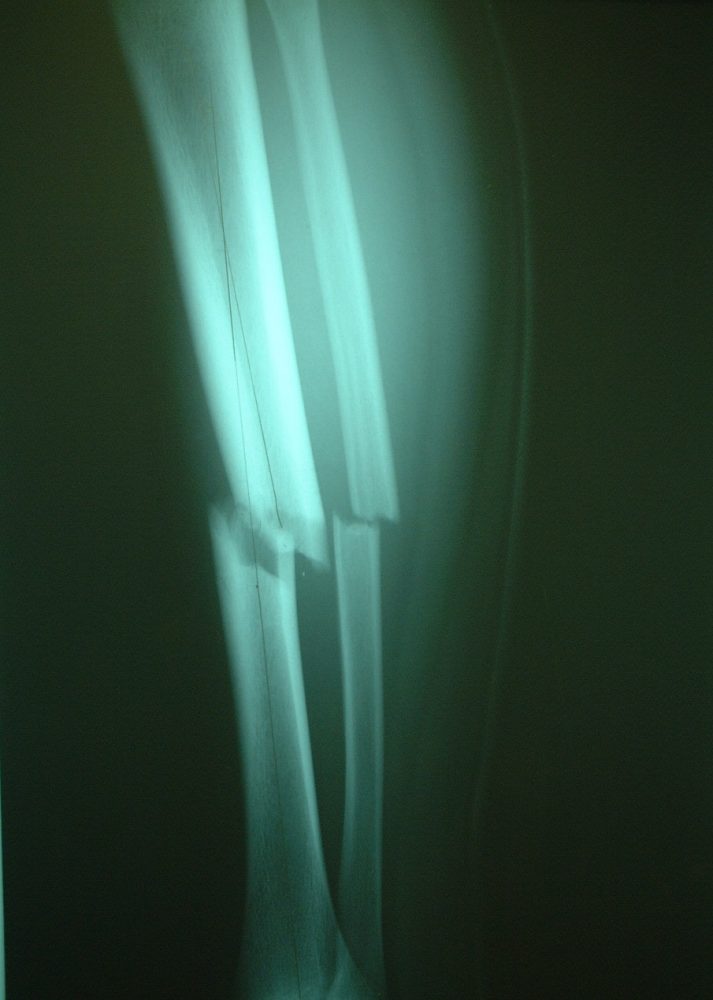

写真2 写真1のレントゲン像。脛骨、腓骨は骨幹部でらせん状骨折を呈している側面像であるが、足関節は90度回転して正面を向いている